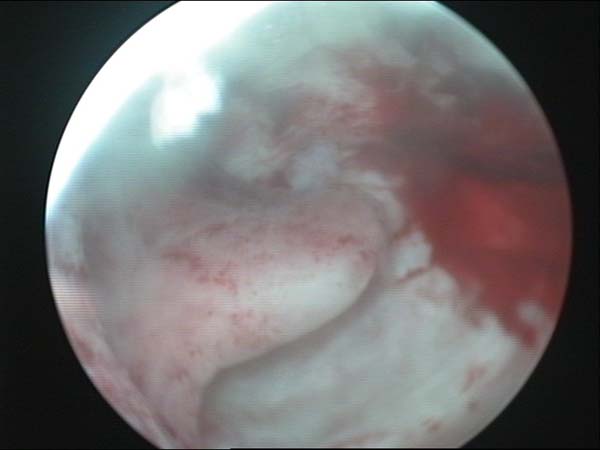

- Hysteroscopy Video clips

- Hysteroscopy Photos

Hysteroscopy Pictures | Dr N Layyous